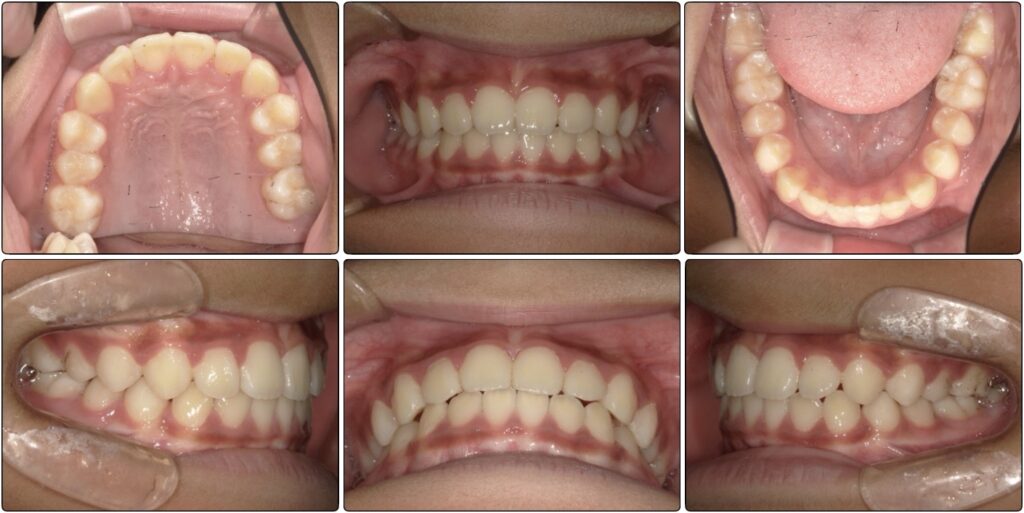

3番目の歯が抜けて生え変わる頃にグッと噛み合わせが変化して、下の歯も並びました。

マウスピースとアクティビティーでここまで変化しました!

また、前歯が大きいと言われていたことが気になっていましたが顎も大きくなって正しく並んでいると大きく感じなくなります。